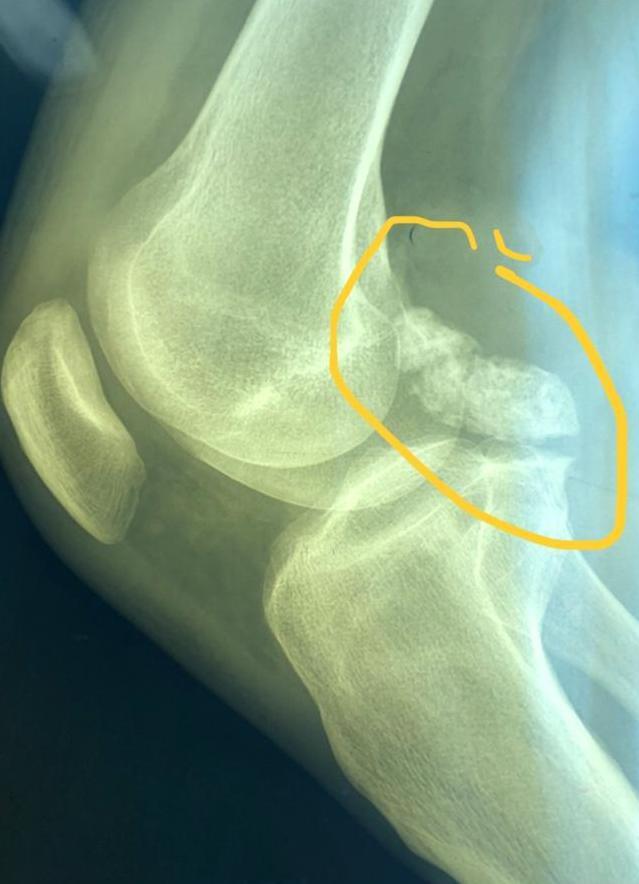

травмы - повреждение менисков (чаще задний рог медиального мениска), разрывы передней крестообразной связки.

остеоартрит.

Что важно не пропустить?

- ЗНО (саркома) - опухоль, которая развивается из клеток оболочки сустава, имеет крайне агрессивное течение, на начальных этапах заподозрить сложно, проявления могут быть неспецифичны - болезненность в области колена, отечность, боли в ночное время, потом появляются общее недомогание, озноб, слабость, потеря массы тела.